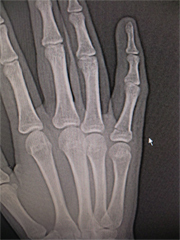

12月は手関節

手関節は足関節と同様にケガの多い部位である。

人は転倒してしまう!と思った瞬間、防御反応で手を出してしまい、

ひねったり、打ったりして受傷するケースが多いです。

今回もスポーツを種目としては、バレーボール・サッカー・ドッヂボール・体育のとび箱などさまざまでした。転倒する時、手が出るのは若い証拠などと言いますが、若不骨折とも言われる橈骨遠位端骨折は、今回2人だけで、多くは経過観察ですんでいました。

また、ギプスするほどではないけれども安静のために、リストサポート固定が各自でつけはずしできるので、好まれています。